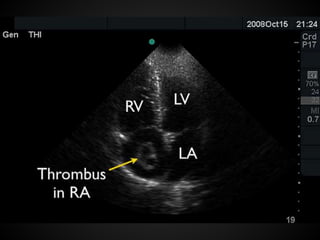

Pericardial Effusion

FAST: subcostal view

Cardiac tamponade: right heart compression

Pericardial Effusion FAST: subcostalview Cardiac tamponade: right heart compression